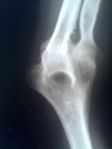

![]() Left elbow-joint, showing anterior and ulnar collateral ligaments. | |

المرفق إنگليزية: Elbow هي عظمة مفصلية تربط عظمة العضد مع عظمتي الزند و الكعبرة. وتكون أماكن الالتقاء الثلاثة، ثلاثة مفاصل أصغر وتسمح هذه المفاصل الصغيرة بحركات معينة، حيث يسمح مفصلا العضد ـ الزند والعضد ـ الكعبرة للشخص بثني الساعد إلى أعلى وأسفل، بينما يسمح مفصلا الكعبرة ـ الزند والعضد ـ الكعبرة بدوران الساعد وكذلك راحة اليد أعلى وأسفل.

يحيط بمفصل الكوع كبسولة من نسيج متين. وتقوم هذه الكبسولة مع عدد من الأنسجة القوية الحبلية الشكل التي تُعرف بالأربطة بالمحافظة على العظام في أماكنها. ويعمل السائل الزيلي بمثابة مزلق لتقليل الاحتكاك عند الكوع.